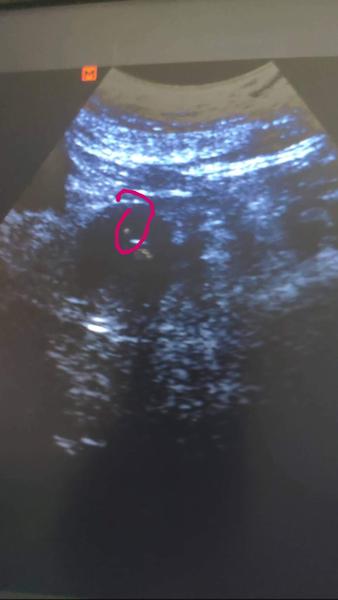

Ahoj holky 👭 ❤️ jak se tady všechny mate? Jak pokračujete? Minulý týden potvrzeno hcg 2000 ❤️ zítra první ultrazvuk tak jsem nervózní 😓, snad bude vše jak má 🙏 🍀